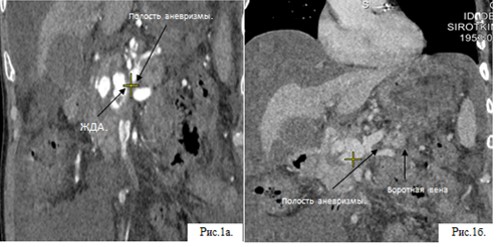

КТ в режиме болюсного контрастирования. Заключение: в головке поджелудочной железы определяется артериовенозная фистула между желудочно-двенадцатиперстной артерией (a.gastroduodenalis) и кавернозно трансформированной воротной веной, 41х31х39 мм. Множественные порто-кавальные анастомозы из верхней брыжеечной вены (ВБВ) в верхней трети. Достоверных признаков экстравазации не выявлено.

ис.1а. КТА. Артериальная фаза. Фронтальная проекция. Показано сообщение желудочно-двенадцатиперстной артерии (ЖДА) и артериовенозной фистулы (стрелка). Видна шейка ложной аневризмы, находящейся в головке поджелудочной железы.

Рис.1б. КТА. Венозная фаза, фронтальная проекция. Сообщение артериовенозной фистулы с портальной системой (стрелки).